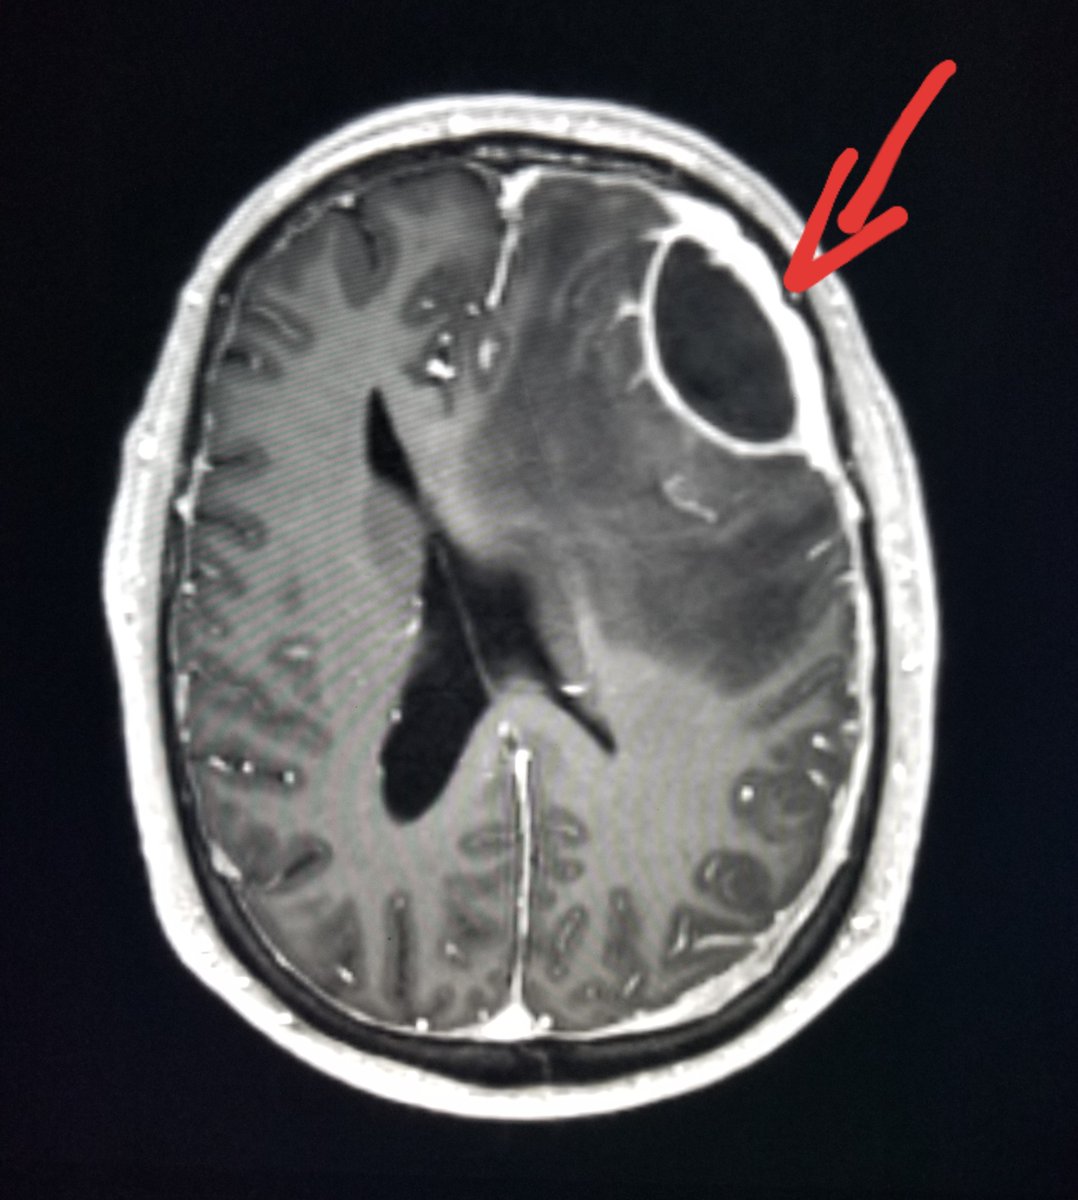

#Brain#MRI: large#abscess (#empyema) in patient after#neurosurgery.#radiologist#radiology This information is for educational purposes. There is no individually identifiable health information. De-identification of protected health information has been performed.pic.twitter.com/gqmwikulGQ